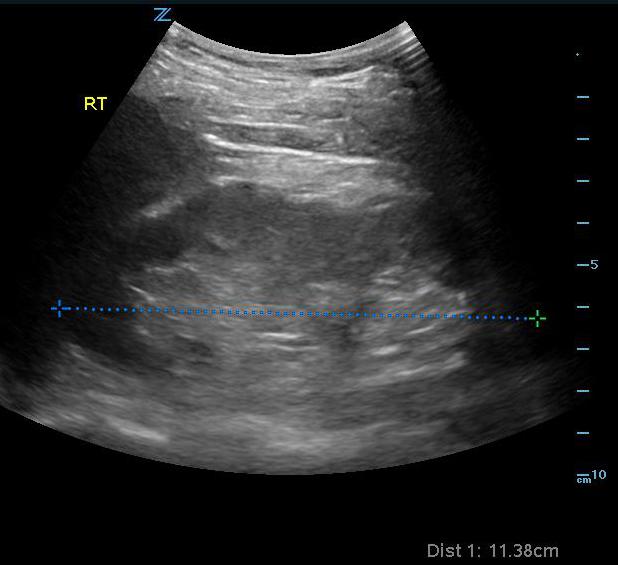

- Figure 1. Measurement of normal right kidney in longitudinal view

- Length of 9-12 cm and width of 4-5 cm in the normal adult. The left kidney is often slightly larger than the right, but both should be within 2 cm of each other.